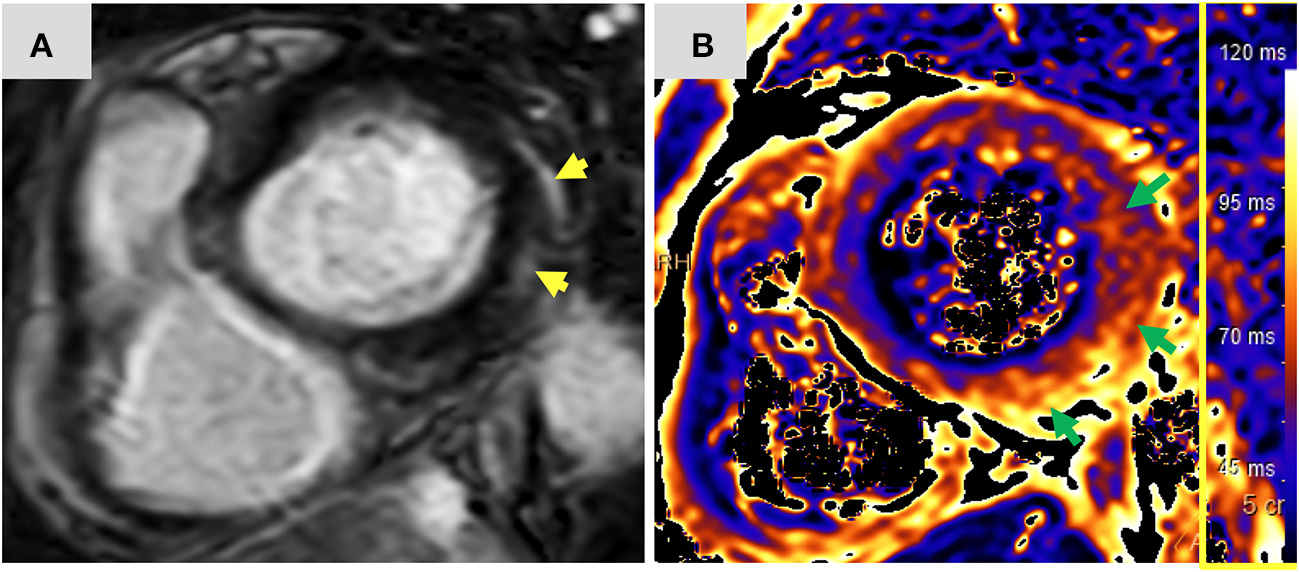

Twelve-days after her first monotherapy treatment with humanized IgG4 anti immunoglobulin-like transcript 3 (ILT3) [MK-0482, MERCK (MSD)] (75 mg), the patient presented to the Hemato-Oncology Ambulatory Care Unit in the Davidoff Cancer Center, Rabin Medical Center (Israel) with fever and malaise (patient's presentation and management time-line is presented in Figure 1). Physical examination was unremarkable and vital signs were in normal range except for systemic fever (temperature 101.3 °F (38.5°C). Laboratory analysis demonstrated 2.1 K/micl leukocytes (normal-range values 4.5–11 K/micl) with 0.2 K/micl neutrophils (normal-range values 1.8–7.7 K/micl), hemoglobin 8.5 g/dL and platelets 12 K/micl. C-reactive protein was 17.3 mg/dL (normal-range values 0.0–0.5 mg/dL). Chest x-ray was normal and 12-leads electrocardiogram (ECG) revealed sinus rhythm with a T-wave inversion in aVL. On a working diagnosis of neutropenic fever, blood cultures were collected and empirical antibiotic (Meropenem) was initiated. COVID-19 status was negative. On day 2, the patient began complaining of a constant chest pain which exacerbated with breathing and was not relieved by oral analgesics. She denied any shortness of breath, palpitations or muscle pain. Blood pressure was 83/52 mmHg, pulse 107/min, oxygen saturation was 96% on room air, respiratory rate 20 breaths per minute. Repeated ECG was unchanged. Lungs were clear to auscultation bilaterally and heart sounds were rapid with no apparent new murmurs. The patient did not show signs of volume overload or pulmonary congestion. Neurologic examination was unremarkable. Troponin T level and NT pro-BNP level were 671 ng/L (normal-range values 0–14 ng/L) and 5,885 pg/ml (normal-range values below 125 pg/ml), respectively. Echocardiography demonstrated a lower limit of normal left ventricular systolic function (LVEF 55%) similar to her prior routine echocardiogram study performed 3 months earlier. Given her clinical presentation and recent novel immunotherapy treatment, the leading diagnosis was immunotherapy-induced acute myocarditis, and decisions were made to monitor her in the cardiac unit and to immediately initiate therapy with empirical pulse dose steroids (methylprednisolone 1 g for 3 days). Cardiac computed tomography revealed normal coronary arteries and ruled out acute pulmonary embolism. On day 3, the patient reported an improvement in her wellbeing and the amelioration of her chest pain. Blood pressure stabilized (103/85 mmHg) and laboratory analysis showed declining levels of cardiac biomarkers (Troponin T 224 ng/L and NT pro-BNP 5,815 pg/ml). The diagnosis of acute myocarditis was confirmed using cardiac magnetic resonance imaging (Figure 2) based on the updated Lake Louis criteria demonstrating subepicardial and mid-wall late gadolinium enhancement in the basal infero- and antero-lateral segments with increased values of native T1 time and T2 time revealing extensive diffuse myocardial edema. After the completion of 3 days of pulse steroid therapy, the patient was switched to oral high-dose (1 mg/Kg) prednisone treatment. Elaborated diagnostic work-up for infectious etiology which included blood cultures, inspiratory viral PCR panel and bacterial, rickettsial and viral serologies was unrevealing.

Figure 2

Magnetic resonance imaging findings: Short axis view (A) of late gadolinium enhancement illustrates sub-epicardial and mid-wall late gadolinium enhancement in the basal infero-lateral and antero-lateral segments (yellow arrows). The corresponding short axis view of T2 mapping (B) illustrates extensive diffuse interstitial myocardial edema (green arrows). Diffuse T2 value was 56.2 ms and focal T2 value in the infero-lateral segment was 61 ms (normal limit 55 ms). The presence of myocardial injury and extensive edema support the diagnosis of acute myocarditis according to the 2018 updated Lake Louise criteria. ms, miliseconds.